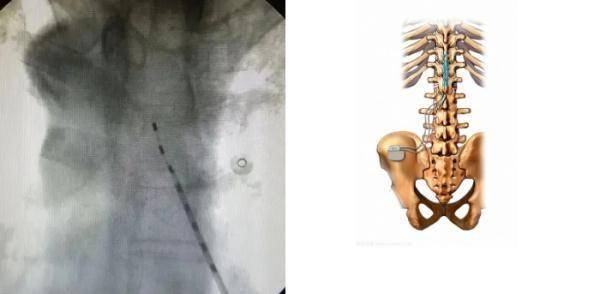

找到根源后

医生安排高大叔

接受脊髓电刺激术(SCS)治疗

经过10几天治疗

高大叔也已经痊愈出院

文章图片